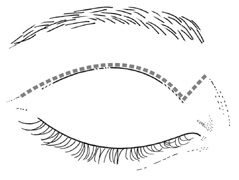

Fig. 6. Lateral orbitotomy through upper eyelid skin crease A. Photo demonstrating right globe ptosis present for more than 2 years. B. Axial CT scan showing a well outlined oval lesion in the lacrimal gland

fossa. C. Coronal CT showing lesion pushing globe inferiorly. D. Skin crease excision marked for lateral orbitotomy. E. Lateral orbital rim exposed. Bone cuts made above frontozygomatic suture

and at zygomatic arch. F. Lateral wall removed. Subperiosteal space exposed. Hard tumor could be

palpated in area of lacrimal gland. G. Benign mixed tumor of lacrimal gland removed. H. Bone sutured into place. I. Skin crease closed. |